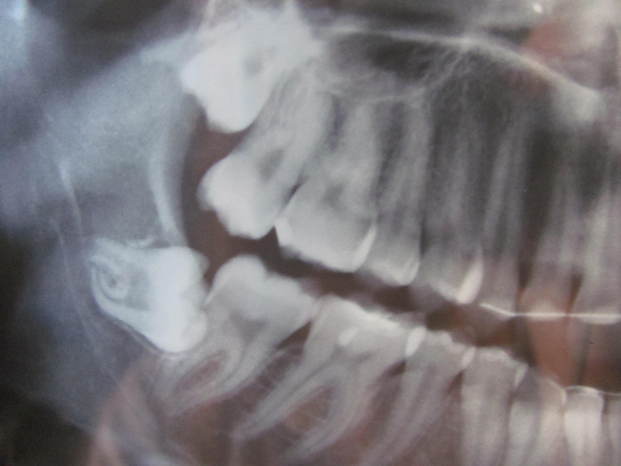

Il dente incriminato, lo vedete? E' in orizzontale.

Avendo la bocca piccola, non è riuscito ad uscire ed è cresciuto in quel modo.

Intanto ho i "denti storti", ma veramente. Non un pochino, come spesso capita a coloro che non hanno portato l'apparecchio dentale, i miei sono proprio in orizzontale!